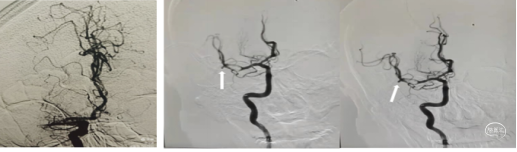

脑血管造影:左侧颈内动脉C 1段呈火苗样,考虑T型段闭塞可能。右侧颈内动脉通过前交通向左侧大脑中动脉区域代偿供血。后交通向左侧大脑中动脉区域供血。可能考虑FLER已经出现病灶,未进行急性血管开通。

错过了最佳治疗血管内介入。

治疗后转康复科,进行康复治疗。康复治疗中停双联抗血小板治疗,又错失了最佳双抗治疗。

患者出现意识不清,病情加重。查CT左侧大脑中动脉区域水肿,低密度改变,中线移位。为大脑中动脉闭塞后改变,恶性脑水肿。

重症脑血管病管理:经甘露醇、白蛋白、3%氯化钠脱水、高压氧、依达拉奉、吡拉西坦脑保护治疗13天水肿消退,脑中线无移位,左侧大脑中动脉区域较前变淡。脑沟脑回显示清楚。